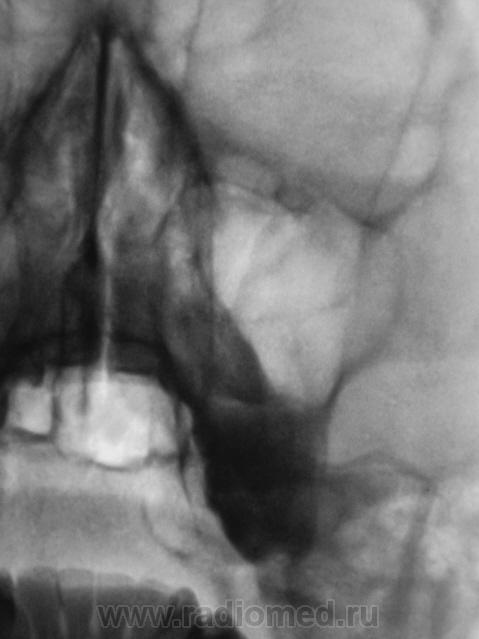

Томограммы.

Ну вот-а я и не знаю шо Вы волновались)) (Линейка -тема!)

Вопросы: 1) с какой целью делали томограмму? 2) достигнута ли цель?

Томограмма получилась еффектным гвоздем " в темечко"....в споре...вернее - в гайморовую полость

По поводу кисты - погорячился, но ни Т-граммы, ни Rg-граммы не исключают жидкость

на дне гайморовых пазух - надо было снимать в носо-лобной проекции!

Вот это обсуждение разрослось вокруг нормы. А зачем томограммы делали?

Рентгенолога в кабинете во время производства снимка не было. У отоларинголога возникли сомнения. Рентген-лаборант произвел томограммы.